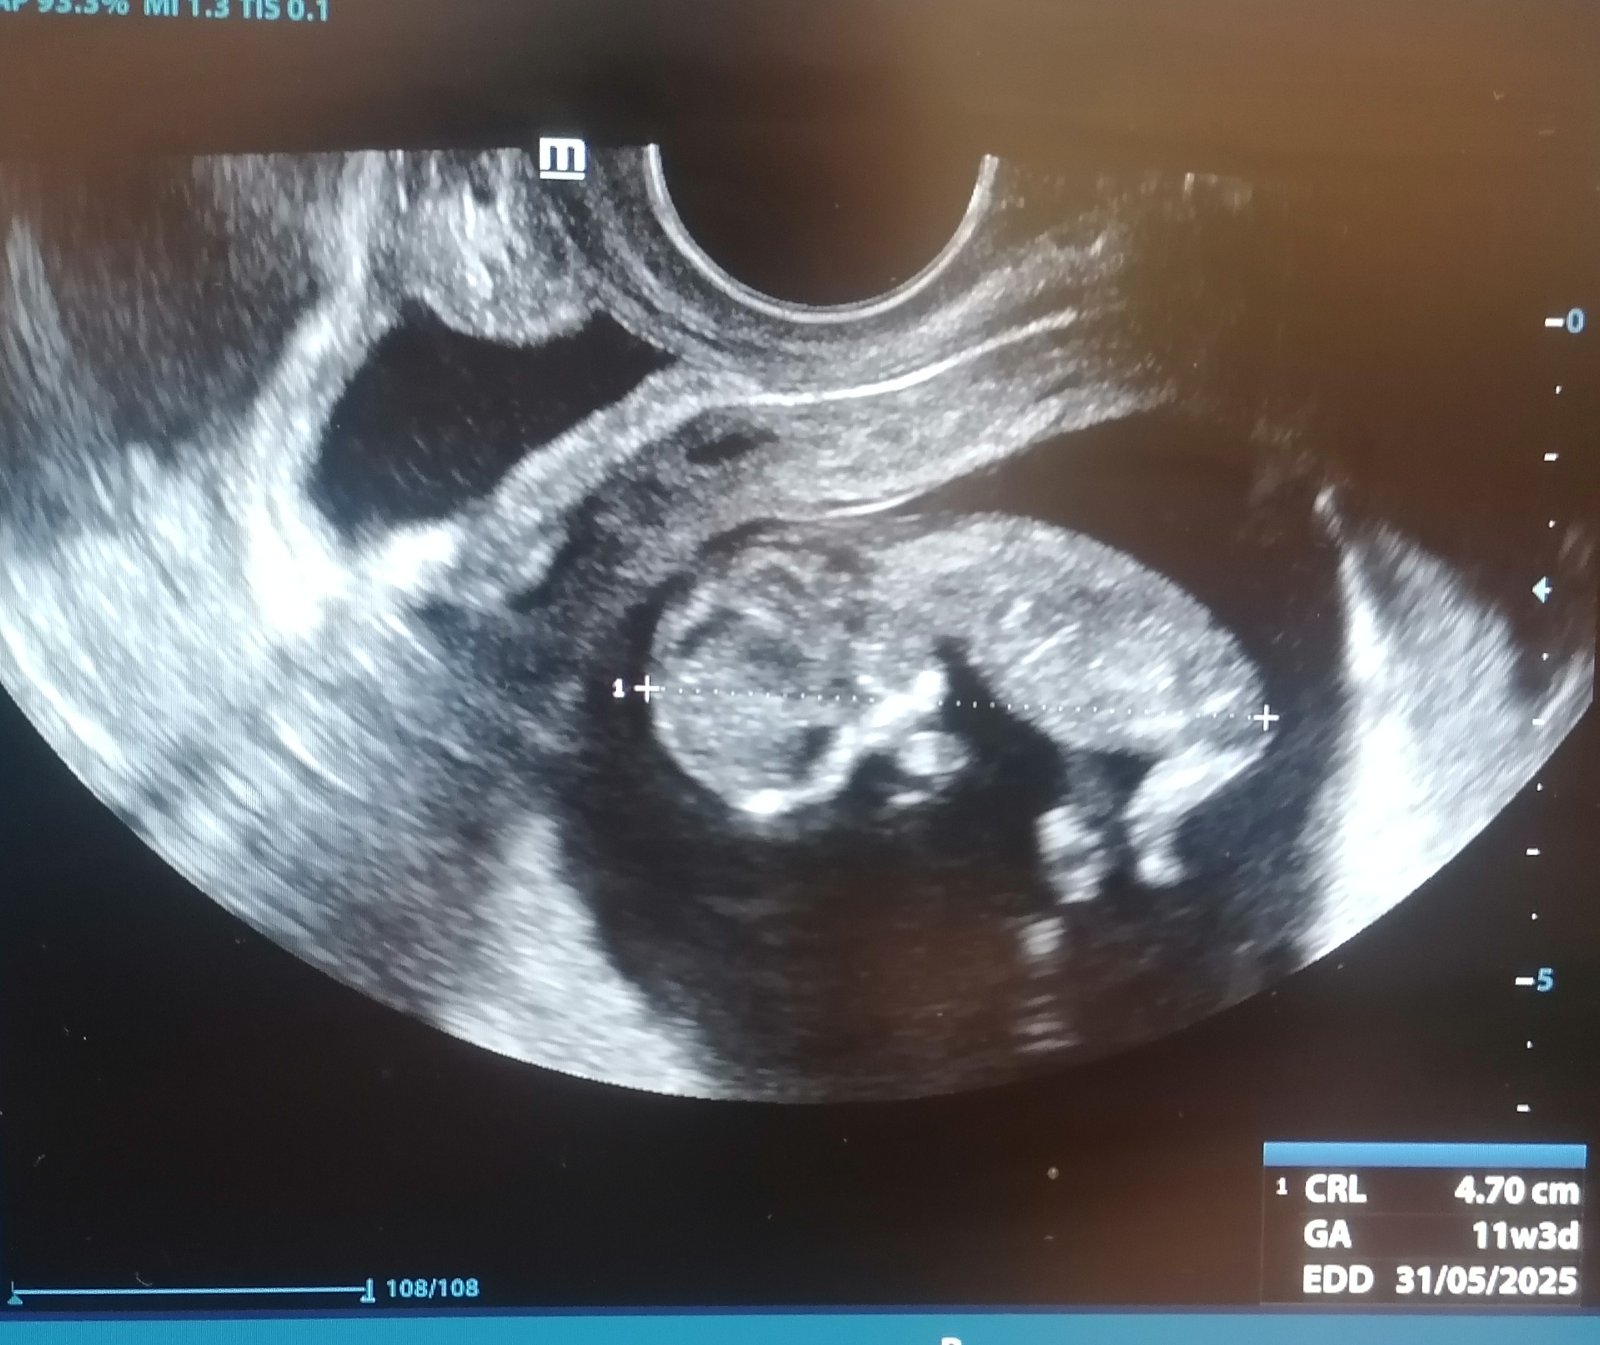

Čo vidíte na ultrazvuku v 11. týždni?

Toto co vidis je tekutina (to cierne, a ohranicene), nevieme z akej pozicie je snimka a kam bola sonda smerovana atd, ale teda urcite tam nemas druhe dieta.

Mne to príde ako močový mechúr 😀 Isto by Dr.v 11tt videl druhý plod, zbytočne sa stresujete vecami, ktorým nerozumiete. Dr. by upozornil, keby sa mu niečo nezdalo.

@michaela329 ano presne ten moc.mechur je moznost alebo proste plod.vak s vodou, len inak "stocena" tj vytvara akoby druhu dutinku na obrazku. Skor ale ten mocak kedze ta stena na fotke je ineho charakteru.